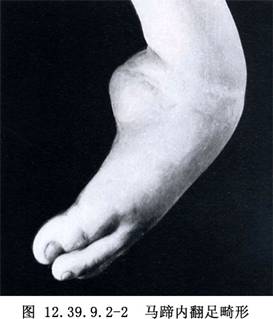

在马蹄内翻足(图12.39.9.2-2)中,增大的距骨头位于足中轴线的外侧并阻碍背屈。做以外侧为基底的距下关节楔形切除术,同时结合中跗关节切除术,以此将距骨头置于足中轴线的稍内侧(图12.39.9.2-1B)。